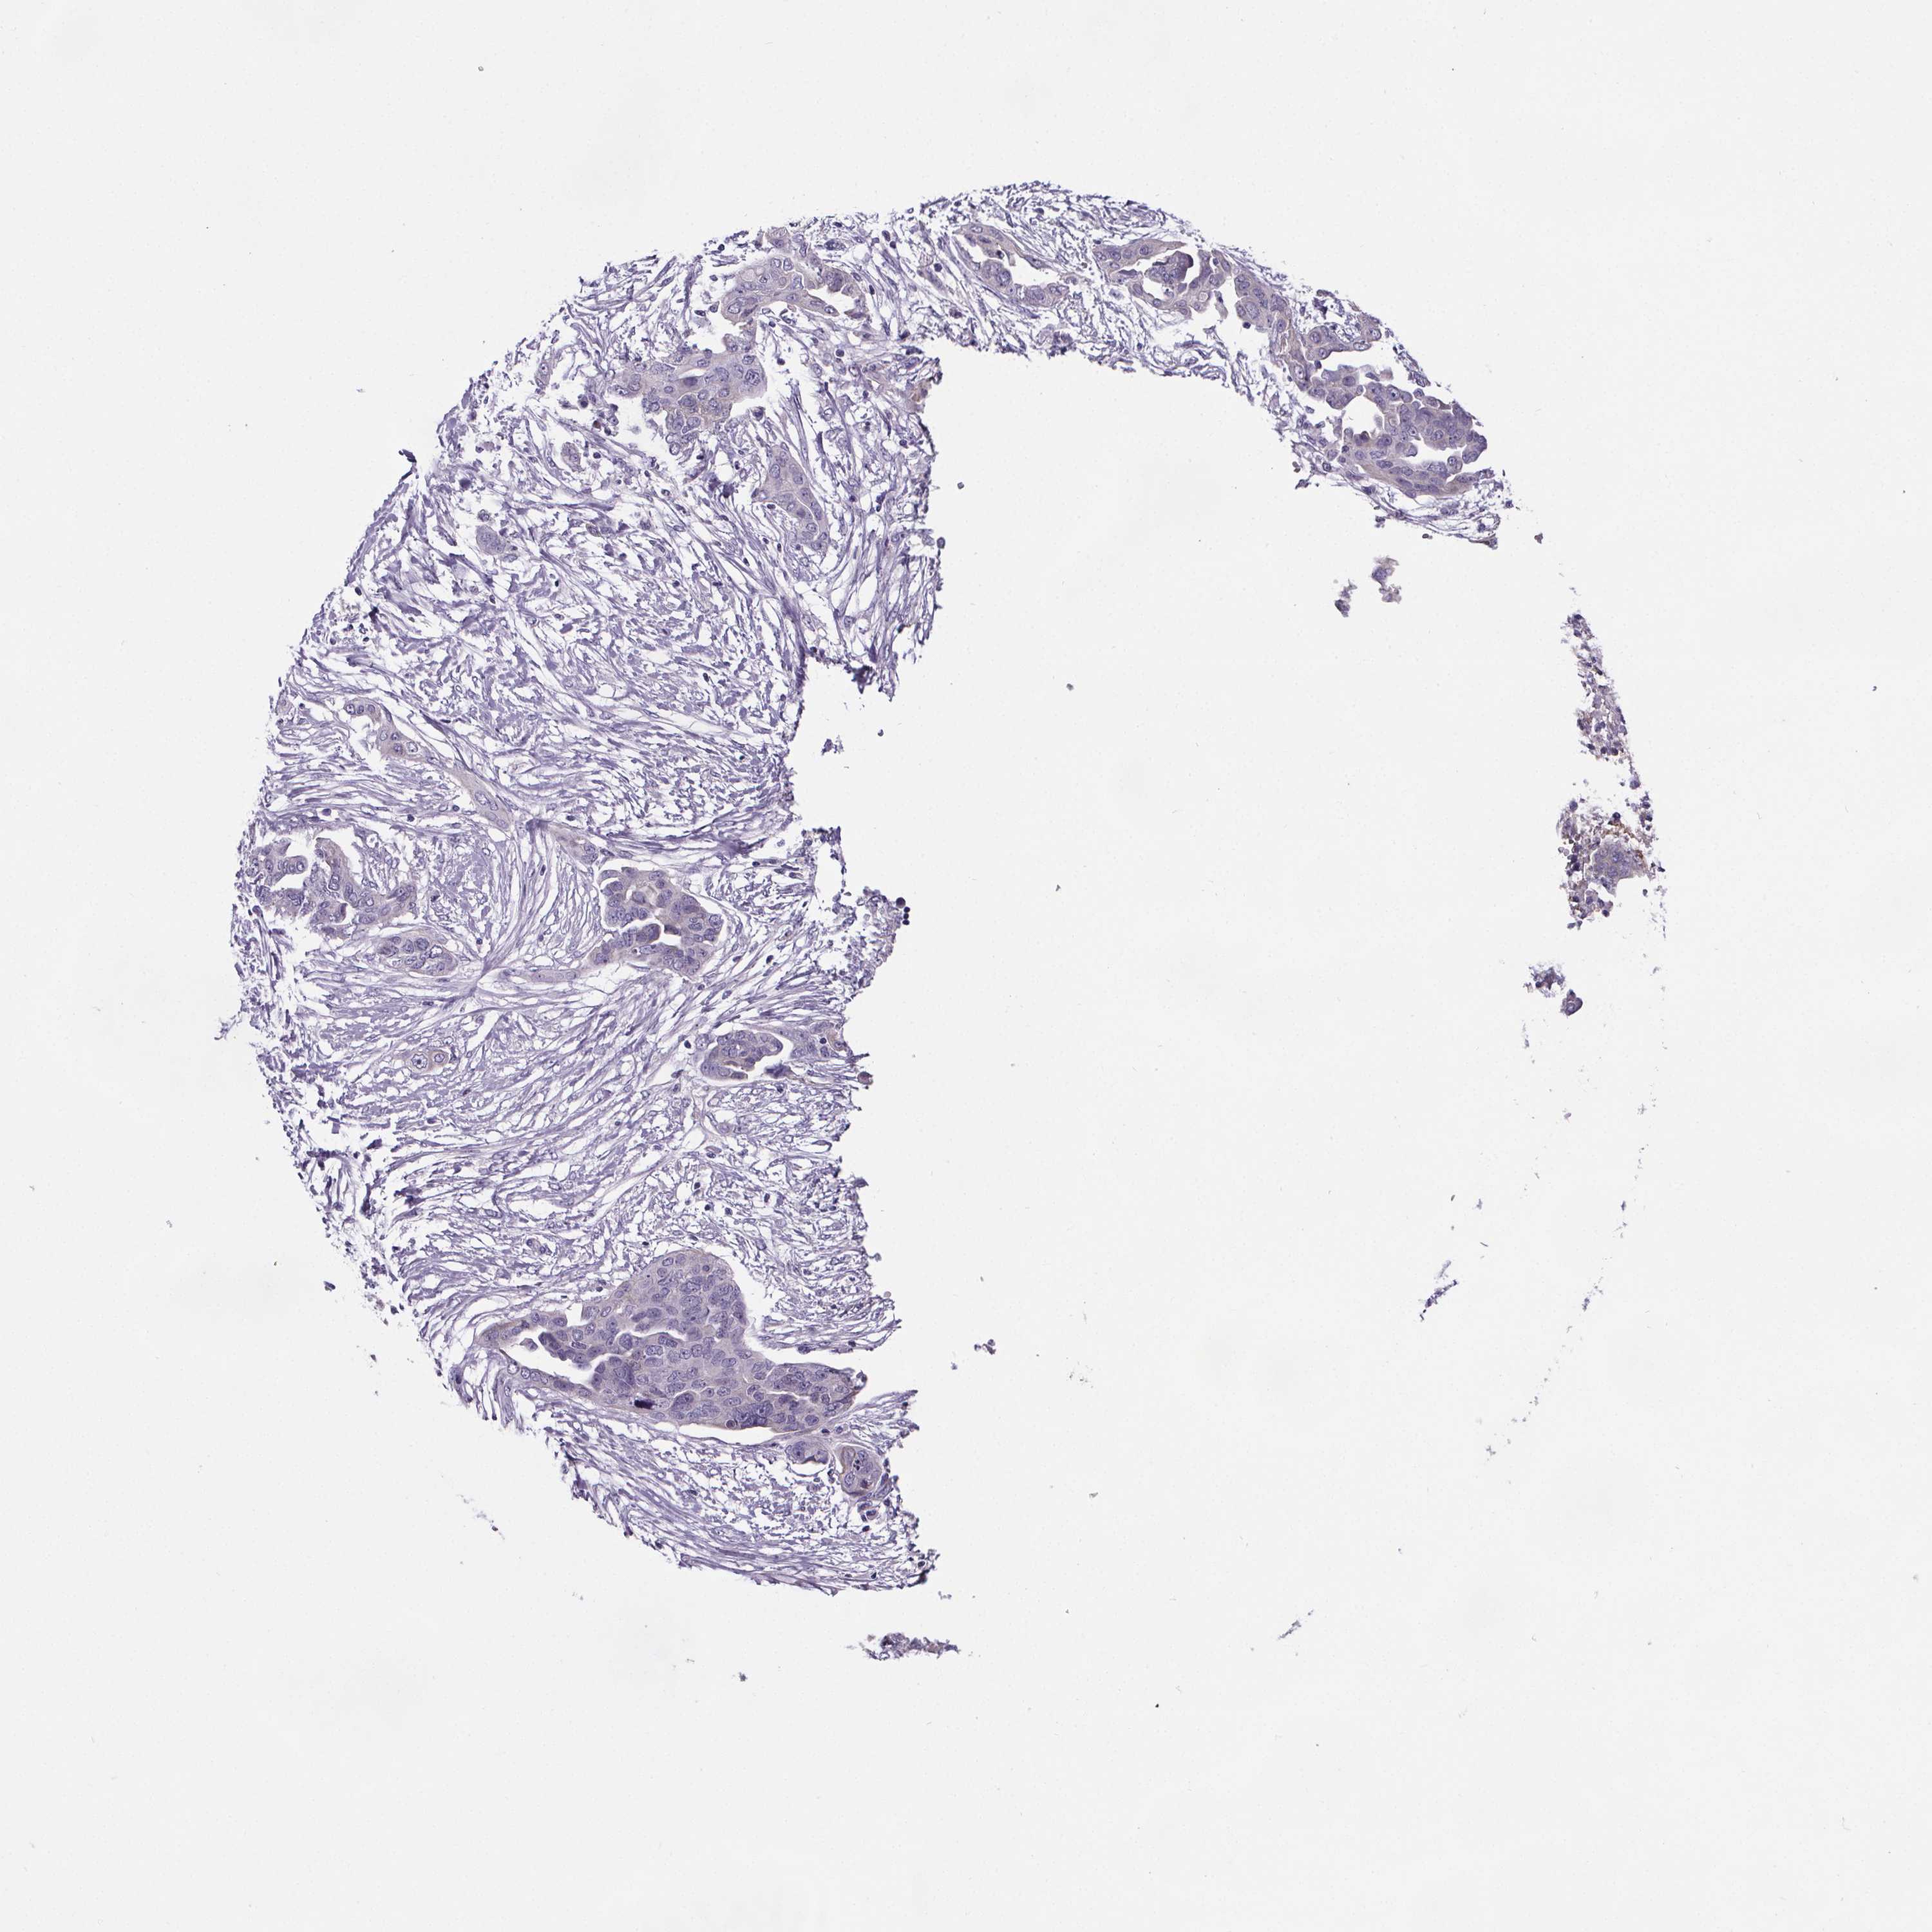

OVARIAN CANCER - Protein expressioni

A mouse-over function shows sample information and annotation data. Click on an image to view it in a full screen mode. Samples can be filtered based on level of antibody staining by selecting one or several of the following categories: high, medium, low and not detected. The assay and annotation is described here.

Note that samples used for immunohistochemistry by the Human Protein Atlas do not correspond to samples in the TCGA dataset.

Antibody stainingi

Antibody staining in the annotated cell types in the current human tissue is reported as not detected, low, medium, or high, based on conventional immunohistochemistry profiling in selected tissues. This score is based on the combination of the staining intensity and fraction of stained cells.

Each image is clickable and will lead to virtual microscopy that enables deeper exploration of all samples and also displays staining intensity scores, fraction scores and subcellular localization as well as patient and tissue information for each sample.

Antibody HPA004133

Antibody HPA043854

Cystadenocarcinoma, serous, NOS

Carcinoma, endometroid